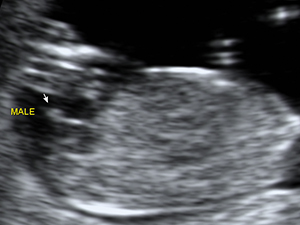

Gender - Male

Male genital organ (arrow) at 18 weeks